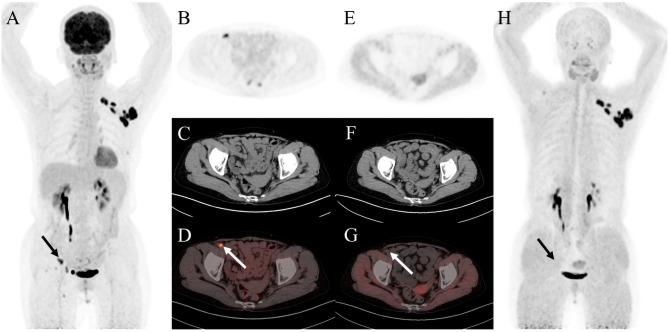

Ga-FAPI (fibroblast activation protein inhibitor) is a novel and highly promising radiotracer for PET/CT imaging. It has shown significant tumor uptake and high sensitivity in lesion detection across a range of cancer types. We aimed to compare the diagnostic value of Ga-FAPI and F-FDG PET/CT in common gynecological malignancies.

Thirty-five patients (median age, 57 years [interquartile range], 51-65 years) were evaluated. In treatment-naive patients (n = 27), Ga-FAPI PET/CT led to upstaging of the clinical TNM stage in five (19%) patients compared with F-FDG PET/CT. No significant difference in tracer uptake was observed between F-FDG and Ga-FAPI for primary lesions: breast cancer (7.2 vs. 4.9, P = 0.086), ovarian cancer (16.3 vs. 15.7, P = 0.345), and cervical cancer (18.3 vs. 17.1, P = 0.703). For involved lymph nodes, Ga-FAPI PET/CT demonstrated a higher SUV for breast cancer (9.9 vs. 6.1, P = 0.007) and cervical cancer (6.3 vs. 4.8, P = 0.048), while no significant difference was noted for ovarian cancer (7.0 vs. 5.9, P = 0.179). Furthermore, Ga-FAPI PET/CT demonstrated higher specificity and accuracy compared to F-FDG PET/CT for detecting metastatic lymph nodes (100% vs. 66%, P < 0.001; 94% vs. 80%, P < 0.001). In contrast, sensitivity did not differ significantly (97% vs. 86%, P = 0.125). For most distant metastases, Ga-FAPI exhibited a higher SUV than F-FDG in bone metastases (12.9 vs. 4.9, P = 0.036).

Ga-FAPI PET/CT demonstrated higher tracer uptake and was superior to F-FDG PET/CT in detecting primary and metastatic lesions in patients with common gynecological malignancies.